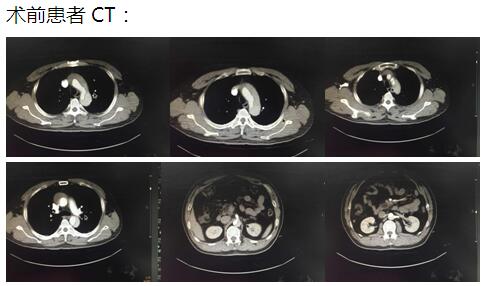

患者是一位48歲中年男性,因胸痛1小時(shí)入院,我院CT提示主動(dòng)脈夾層累及胸、腹主動(dòng)脈全層,診斷為主動(dòng)脈夾層(D ebaKey I型)?;颊卟∏槲V兀中g(shù)治療是挽救其生命的唯一希望。為了挽救病人生命,經(jīng)過麻醉科、手術(shù)室、體外循環(huán)組的術(shù)前充分討論,心胸外科廖金文主任、廖承輝副主任帶領(lǐng)團(tuán)隊(duì)決定為其施行復(fù)雜而高難度的淺低溫停循環(huán)下“孫氏手術(shù)”。術(shù)中見主動(dòng)脈全程及三分支受累,右冠受累,冠脈開口受壓狹窄,予以行“升主動(dòng)脈 主動(dòng)脈弓置換 降主動(dòng)脈術(shù)中支架置入術(shù)”,團(tuán)隊(duì)成員歷經(jīng)約10個(gè)小時(shí)的奮戰(zhàn),手術(shù)順利完成。術(shù)后六小時(shí)患者意識完全清醒,現(xiàn)在已完全康復(fù)。